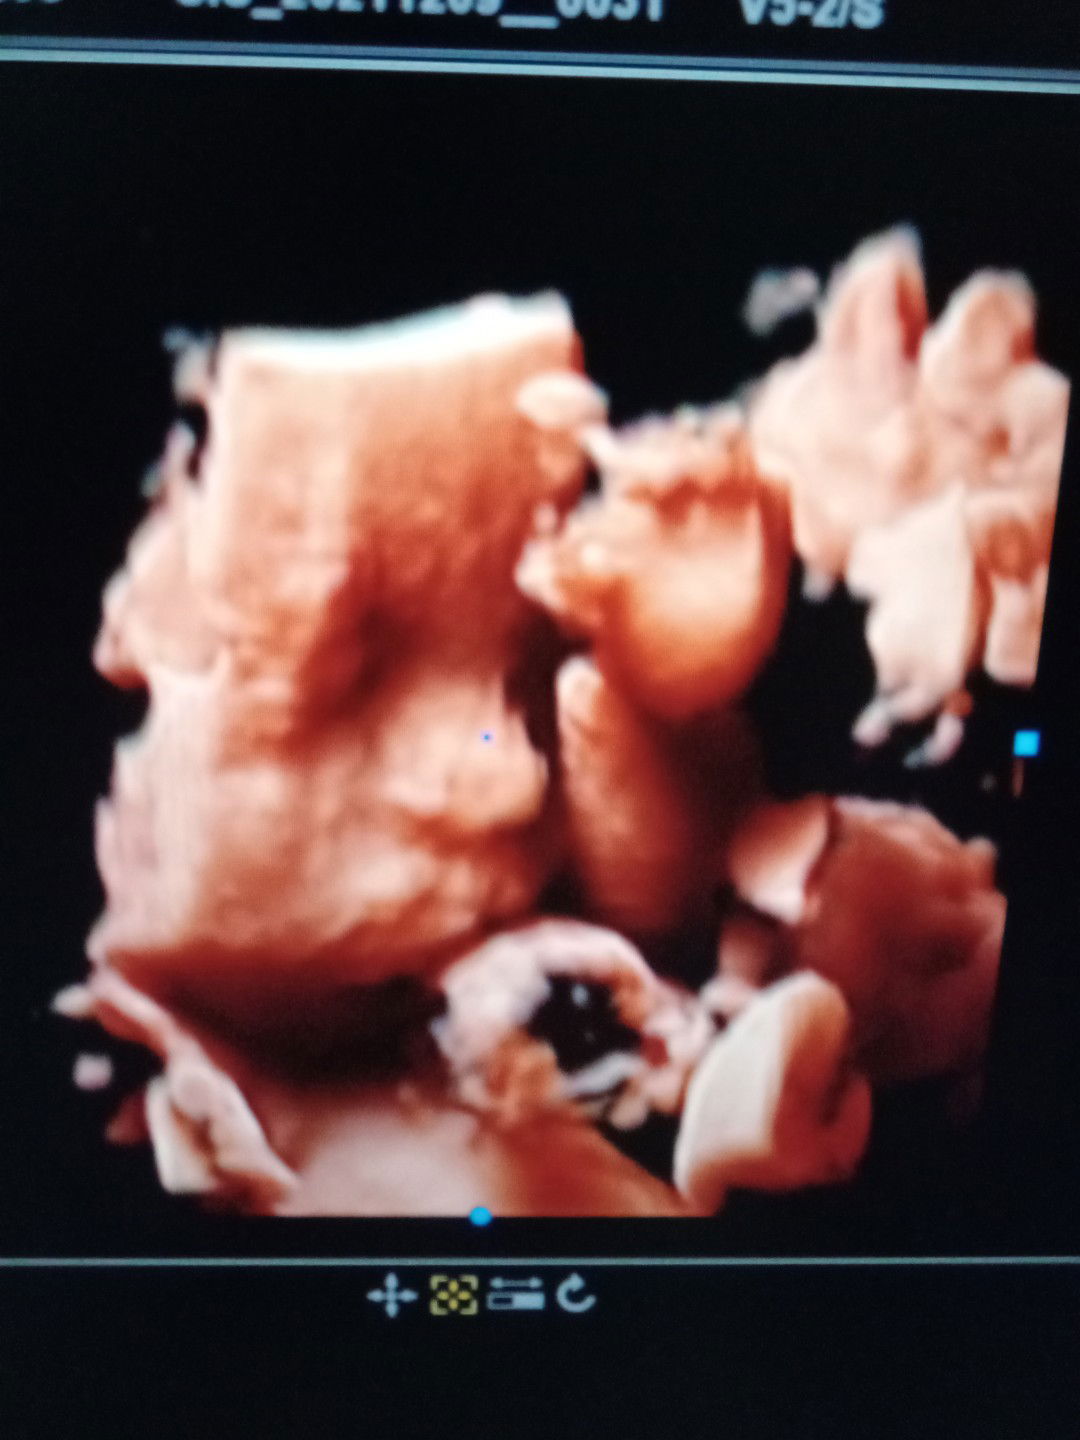

Hpl 17 agustus udah ngerasaain apa aja bun, kalau saya blom ngerasain apaΒ²

saya sdh ngalamin kontraksi palsu bun,rasanya udh seperti mau melahirkan,sakit nya subhanallah nikmat,pas di cek di bidan ternyta kontraksi plsu,saya Hpl 15 Agustus